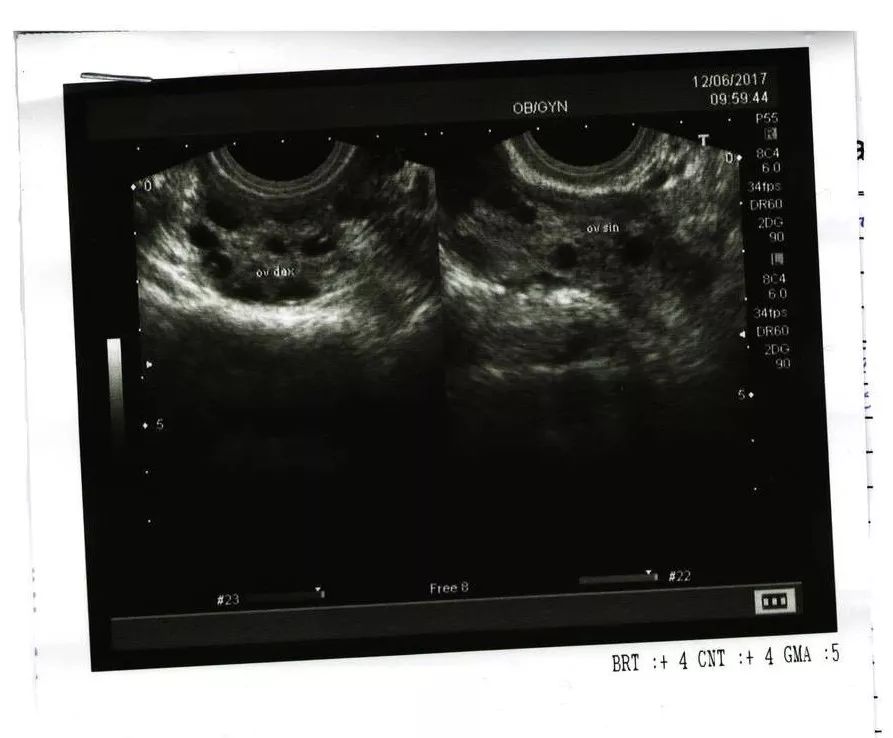

女性在做子宫附件B超的时候,医生看到一侧或双侧卵巢中,直径为2~9毫米的卵泡≥12个,和(或)卵巢体积≥10毫升,就会下卵巢多囊性改变的诊断。

在卵泡的募集、选择期做B超,很有可能就会在卵巢中找到12个以上直径为2~9毫米的卵泡;而且精神压力比较大,情绪不稳定,导致内分泌紊乱、月经失调,也可能会出现一过性的卵巢多囊样改变。

有研究表明,6%~25%的正常女性,卵巢可呈多囊性改变。而且,要是你的月经周期比较规律,那就更不用怕多囊卵巢综合征了。